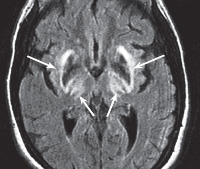

• Нейровизуализация. КТ, МРТ головного мозга визуализируют неспецифичные атрофические изменения, наиболее выраженные в хвостатом ядре, полосатом теле. ПЭТ головного мозга определяет гипометаболизм стриатума, снижение числа дофаминовых рецепторов.